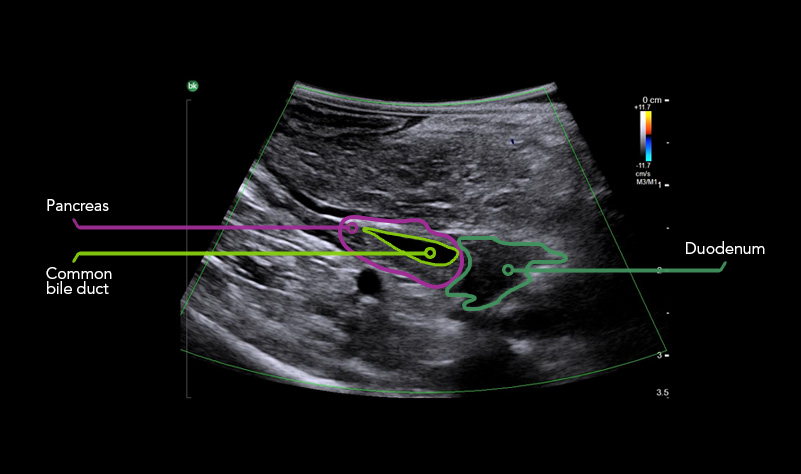

BILIARY TRACT VISUALIZATION

iUS uses color flow doppler to help differentiate between vessels and ducts and is overall effective at imaging difficult cases such as inflammation or fibrosis .1.4 - 6

Gallbladder Adenocarcinoma with Gallstones and Sludge

Gallstone

Bile Duct – Metastatic Tumor With Color Doppler